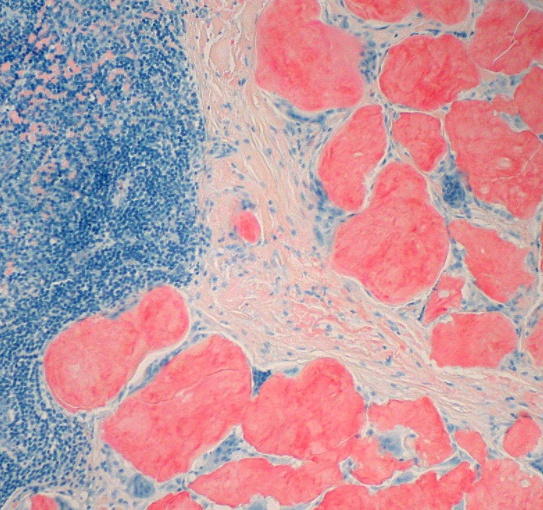

Creutzfeldt-Jakob

round vacuoles in brain

same thing that causes mad cow.,

PrPc normal, everyone has them

PrPsc gets in body and link to normal one, convert it to abnormal

startle to minimal stimuli

know spike wave complexes